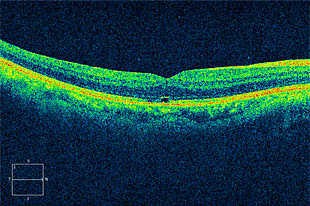

黄斑円孔

網膜の中心である黄斑部に穴が開く病気で、視野の中央が見えにくくなります。

術前写真

術前 OCT

術後写真

術後 OCT